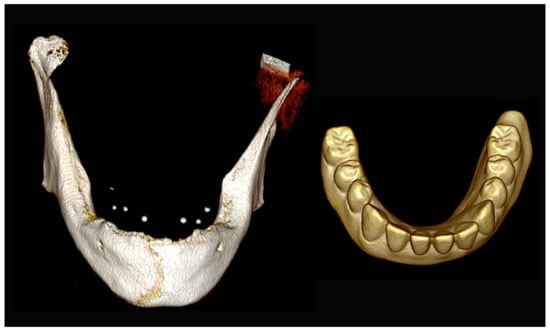

Figure 31.

Three-dimensional (3D) CBCT scan images of the edentulous mandible with the patient wearing the provisional prosthesis and 3D images of the prosthesis equipped with integrated radiopaque reference spheres scanned separately.

Figure 32.

Planning of the number, the diameter, the axis of the implants with respect to the design of the final prosthesis and the trajectory of the inferior alveolar nerves.